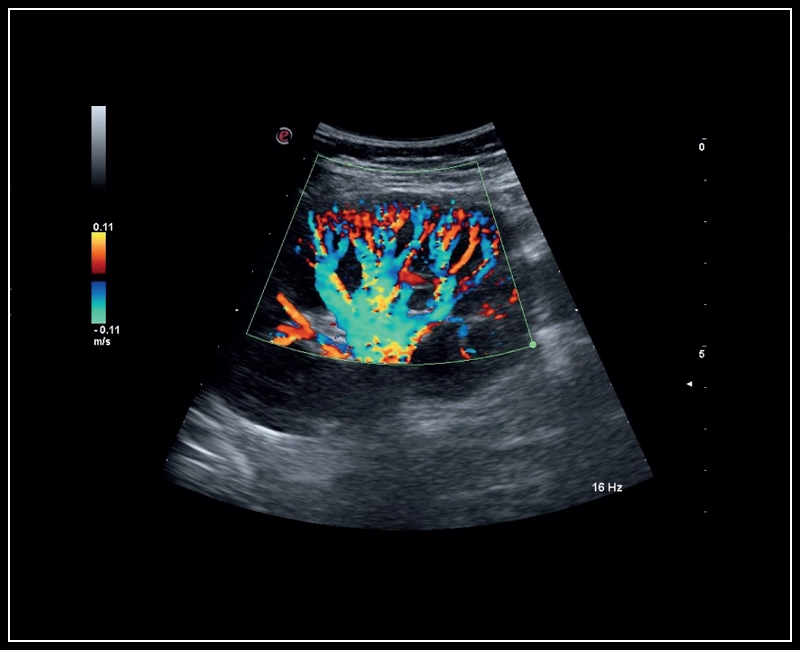

MyLab™9 Platform - XFlow Doppler enhancement in liver vascularization

MyLab™9 Platform - XFlow Doppler enhancement in liver vascularization